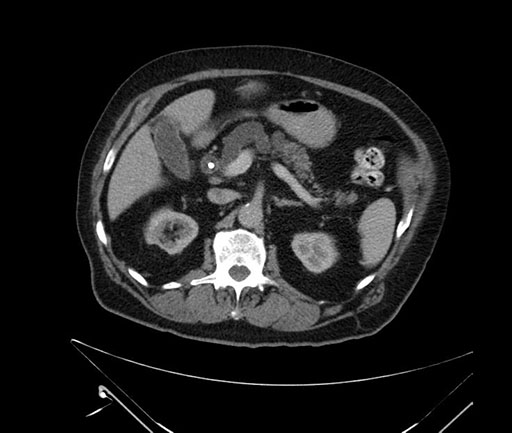

Axial - 3 months prior